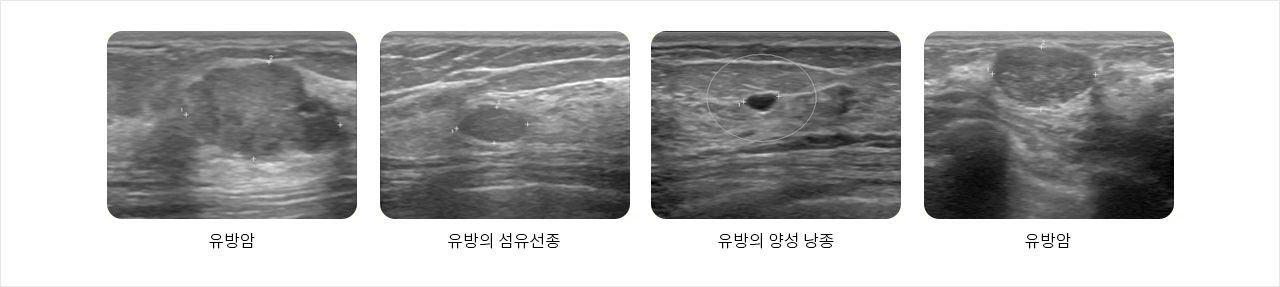

유방 초음파 영상 기술은 최근 몇 년 동안 크게 발달하여 유방촬영술과 임상적으로는 알아내기 힘든 잠복성 병변을 진단할 수 있게 되었습니다. 특히 유방 초음파는 젊은 여성에게서 볼 수 있는 치밀한 유방을 정확하게 진단할 수 있는 탁월한 매체가 되고 있습니다. 유방 초음파 검사는 검사의 방법이 매우 간편하고 검사로 인한 방사선 피폭의 위험이 없으므로 모든 연령층의 여성에게 반복적으로 사용 할 수 있는 검사 방법 입니다. 유방 초음파 검사는 유방 촬영에서는 보기 힘든 물혹이나 양성종양 그리고 악성종양을 비교적 정확하게 감별 진단할 수 있습니다.

우리나라 여성의 유방은 서구 여성에 비해 치밀해서 유방촬영을 하면 유선조직이 하얗게 보이는데 치밀하면 할수록 더 하얗게 보이고 암도 하얗게 보이므로 촬영만으로는 암을 발견하기 어려운 경우가 있어 초음파 검사가 필수적입니다.

특히 30대 이전의 젊은 여성의 경우 유선이 치밀하여 유방촬영상 하얗게만 보이는 경우가 많아 반드시 초음파를 통해 검사의 민감도를 높여야만 정확한 검사가 가능 합니다. 그러나 유방 초음파는 종괴의 감별진단에 탁월하지만 조기암의 지표가 되는 미세석회화는 정확히 보기 어려우므로 유방암의 정확한 조기 검진을 위해서는 반드시 유방촬영과 유방 초음파를 병행하셔야 합니다.

- 유방암

- 유방의 섬유선종

- 유방의 양성 낭종